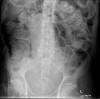

Diverticulosis de colon.

Diverticulosis de colon. Megacolon.